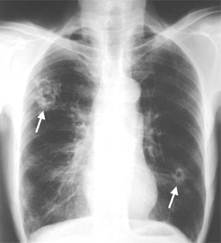

В хронической фазе развивается очаговый фиброз лёгких; рентгенологически выявляют очаги затемнения с просветлениями в центре. Возможны диффузный пневмосклероз, легочное сердце, легочное кровотечение, рак легких. Занос паразитов в мозг приводит к энцефалиту и менингоэнцефалиту, объемному процессу, напоминающему опухоль. При диссеминации яиц возможен полисерозит.

В период миграции личинок специфические проявления отсутствуют. Возможны энтерит, гепатит, доброкачественный асептический перитонит, симптомы аллергии, включая миокардит и кожный зуд. Уже в ранней стадии парагонимоза появляются симптомы поражения легких в виде летучих инфильтратов, воспаления легких, экссудативного плеврита. В дальнейшем процесс в легких прогрессирует, возникают боль в грудной клетке, кашель с большим количеством мокроты с примесью гноя, крови, лихорадка. В хронической фазе развивается очаговый фиброз легких; рентгенологически выявляют очаги затемнения с просветлениями в центре. Возможны диффузный пневмосклероз, легочное сердце, легочное кровотечение, рак легких. Занос паразитов в мозг приводит к энцефалиту и менингоэнцефалиту, объемному процессу, напоминающему опухоль. При диссеминации яиц возможен полисерозит.